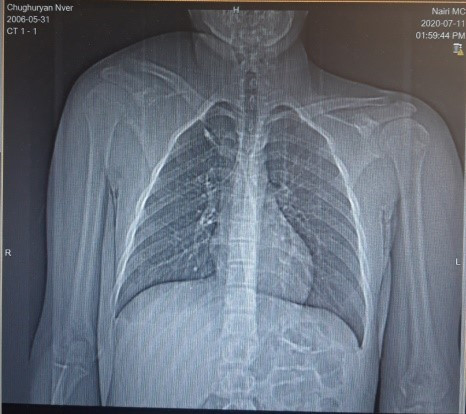

Рисунок 1. Радиологическое изображение лопатки